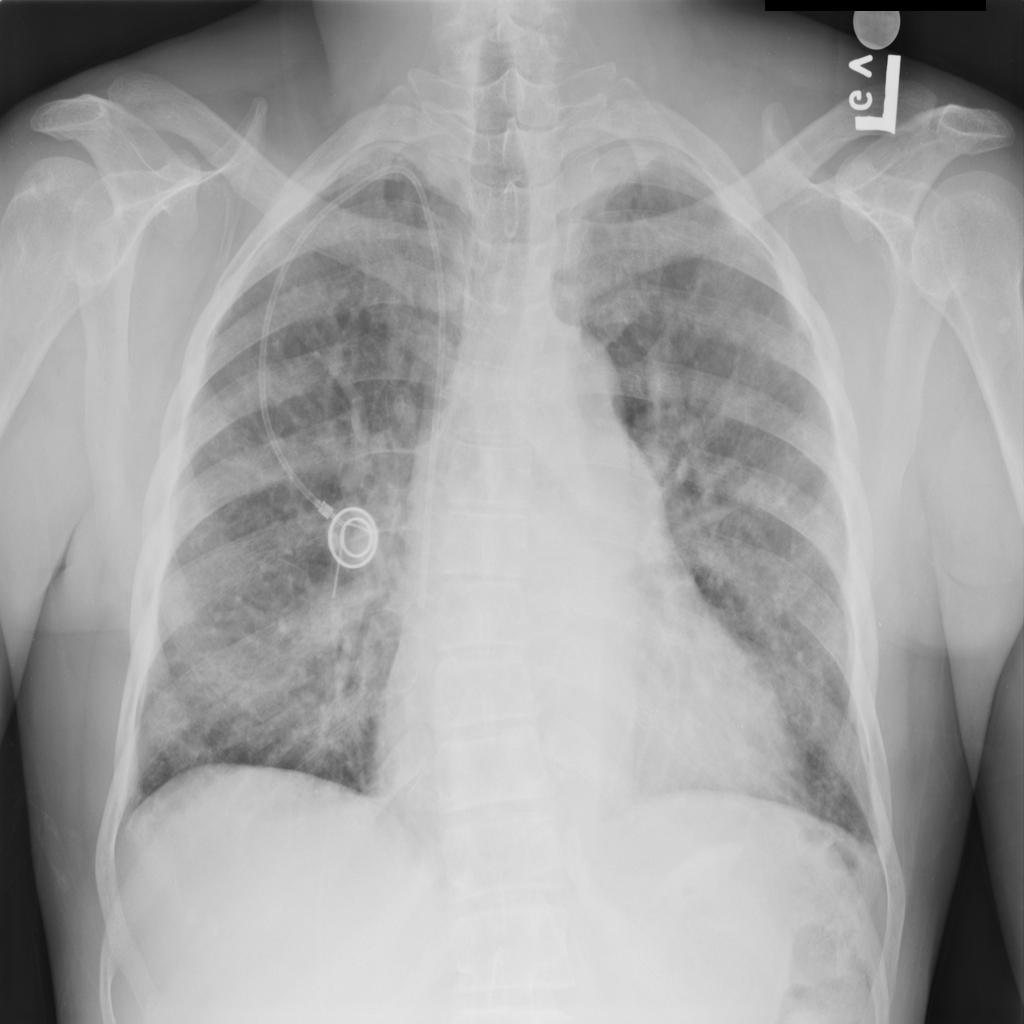

PAT-A5F7 · IMG-002Cardiomegaly

PAT-A5F7 · IMG-002

PA